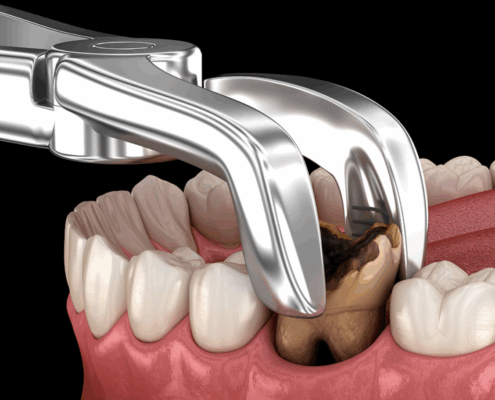

CONSEILS POST-OPÉRATOIRES APRÈS EXTRACTION / DENTS DE SAGESSE